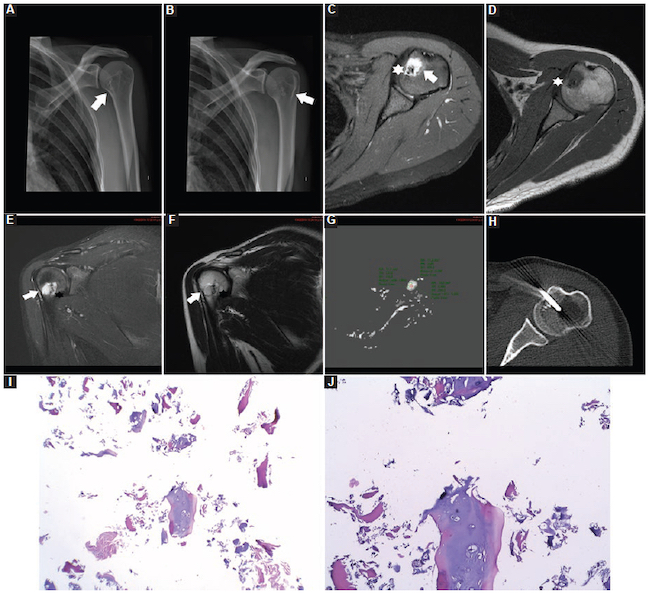

Infección: fueron 12 casos, con un valor medio de CDA de 0,68 ± 0,17 × 10−3 mm2/s (0,40-0,90) (Fig. 8), de los cuales hubo cinco en los miembros superiores, tres en la pelvis, tres en los miembros inferiores y uno en el cuello.

Encondromas: fueron 11 casos, con un valor medio de CDA de 1,65 ± 0,31 × 10−3 mm2/s (1,30-2,10) (Fig. 9), de los cuales fueron cuatro en el fémur, cuatro en el húmero, uno en la tibia, uno en el peroné y uno en la falange.

Lipomas: fueron nueve casos, con un valor medio de CDA de 1,66 ± 0,31 × 10−3 mm2/s (1,30-2,10) (Fig. 10), de los cuales fueron cuatro en los miembros superiores, cuatro en los miembros inferiores y uno adyacente a la parrilla costal.

Quiste óseo simple: fueron nueve casos, con un valor medio de CDA de 2,02 ± 0,54 × 10−3 mm2/s (1,30-2,70) (Fig. 11), de los cuales fueron dos en los miembros superiores, seis en los miembros inferiores y uno en la pelvis.